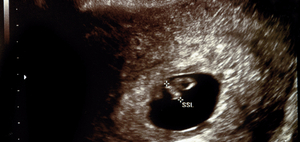

妊娠6週 赤ちゃんのエコー写真 超音波写真まとめ たまひよ

妊娠6週 エコーで赤ちゃんの心拍確認 つわりの症状や過ごし方 ままのて

妊娠2ヶ月 妊娠4週 5週 6週 7週 妊娠初期 の超音波写真 妊娠 出産 育児に関する総合情報サイト ベビカム

妊娠6週0日 6w0d の超音波 エコー 写真